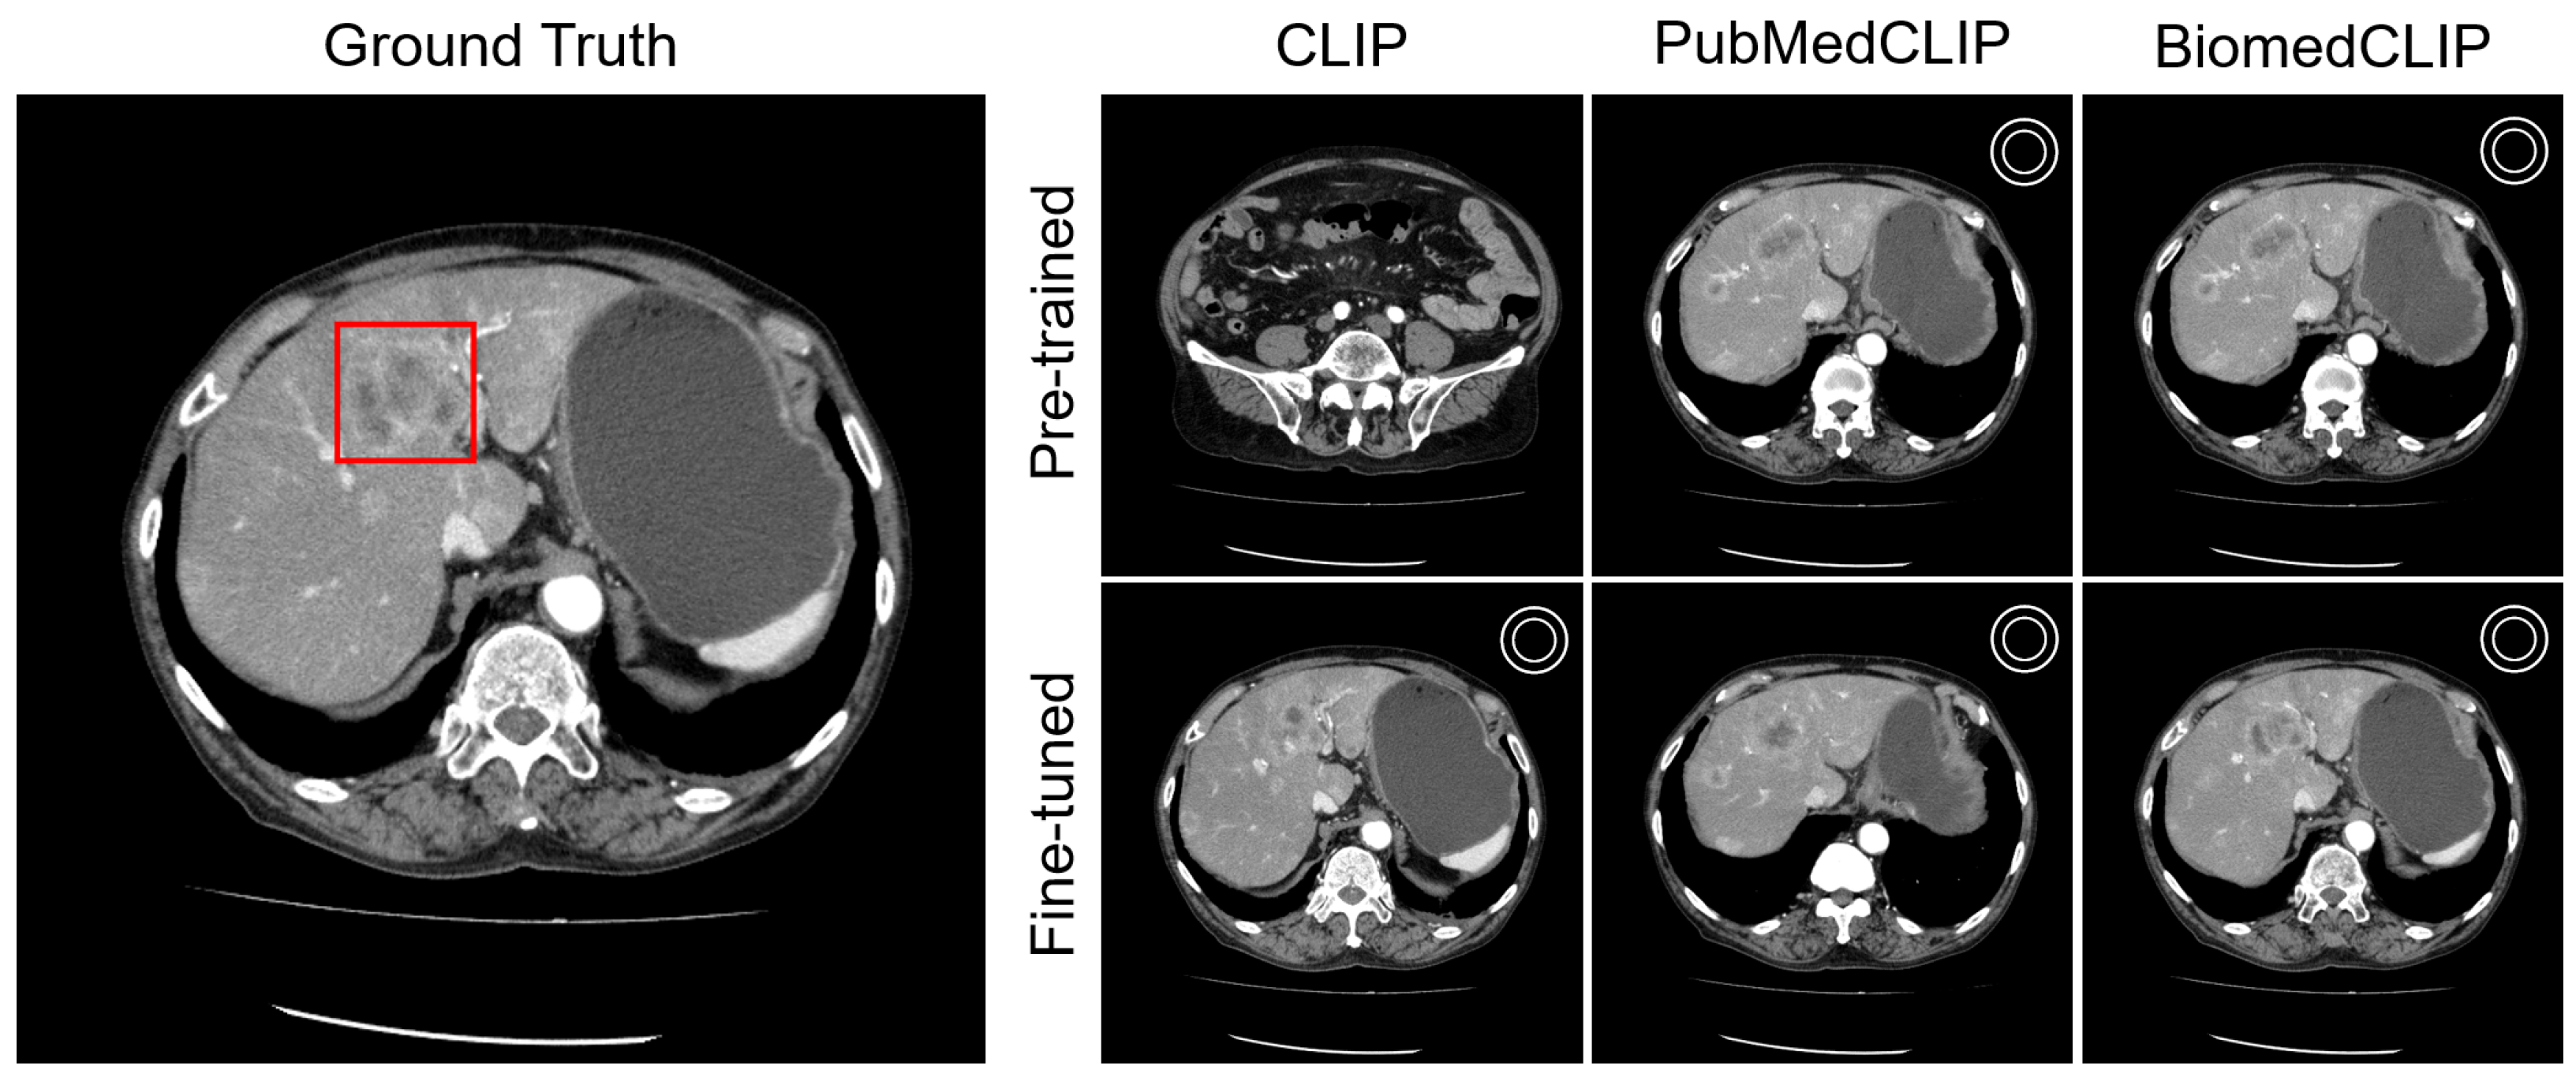

4.4. Visualization

Appendix C. Visualization

Appendix C.1. Lesion Awareness